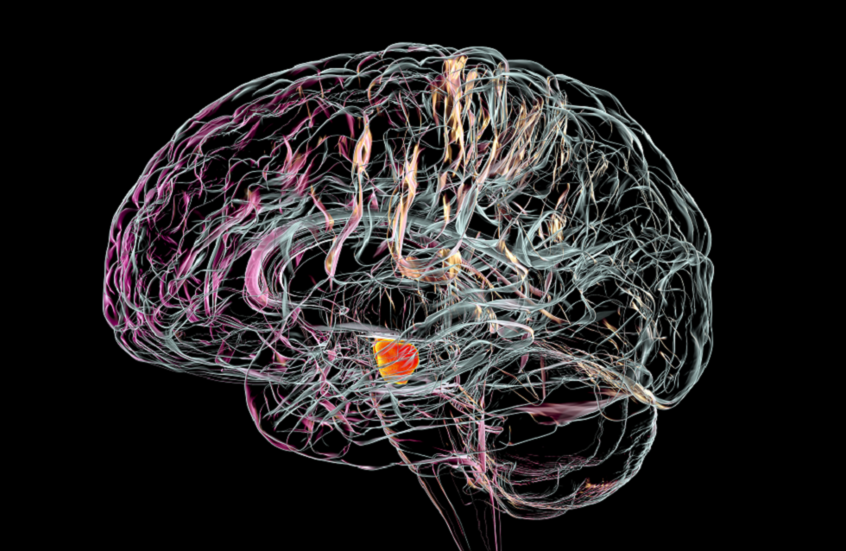

يعد مرض باركنسون اضطرابا تنكسيا متفاقما يؤثر بشكل مباشر على القدرة الحركية للجسم نتيجة موت الخلايا العصبية المنتجة لمادة الدوبامين، وهي ناقل عصبي ينتجه الدماغ ويلعب دورا مهما في عدة وظائف أساسية للجسم والعقل. ومع مرور الوقت، قد يصاب المرضى بتصلب شديد يفقدهم القدرة على الحركة والعناية الذاتية، بينما تركز العلاجات المتوفرة حاليا على تخفيف الأعراض دون معالجة السبب الجذري للمرض.

ويقوم العلاج الجديد على زرع خلايا جذعية مبرمجة لتتحول داخل الدماغ إلى خلايا عصبية منتجة للدوبامين، بهدف إعادة بناء الشبكات العصبية المتضررة.